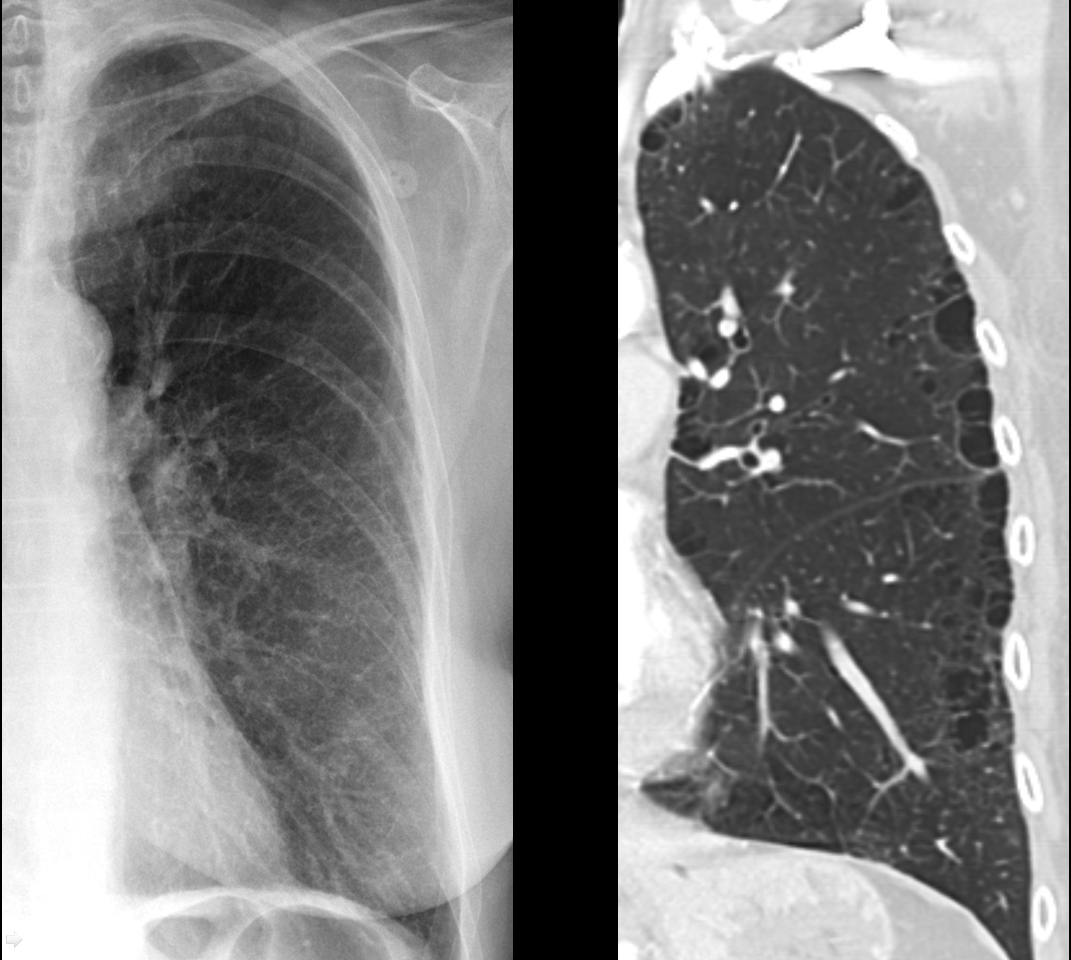

Gallery COPD Subtle paraseptal emphysema

Subtle paraseptal emphysema